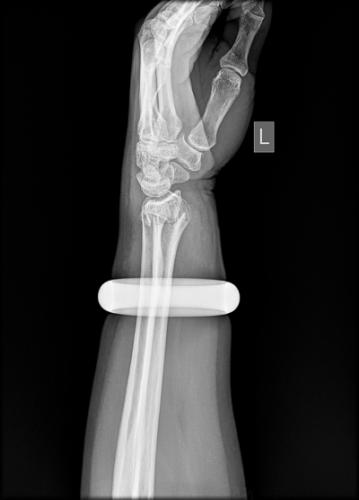

25日早上,57岁的王女士买菜回家时不慎滑倒,情急之下她用左手撑地,很快手腕就肿了起来。邻居听说后,让她赶紧去做做按摩,结果越按越痛,越肿越厉害。下午她找到武汉市第一医院骨科门诊,拍片发现左手桡骨远端骨折。

此时,手镯卡住腕部,不但会加重局部肿胀,还会越勒越紧导致肢体坏死。管床医生石晨尝试用肥皂水、润滑剂等方法取镯,都没能成功。

玉镯贴身戴了七八年,当年花了2万元买的。思虑再三,王女士提出砸碎玉镯,并签字为证。石晨用叩诊锤敲碎了镯子后,当即为她手法复位,打上了石膏。